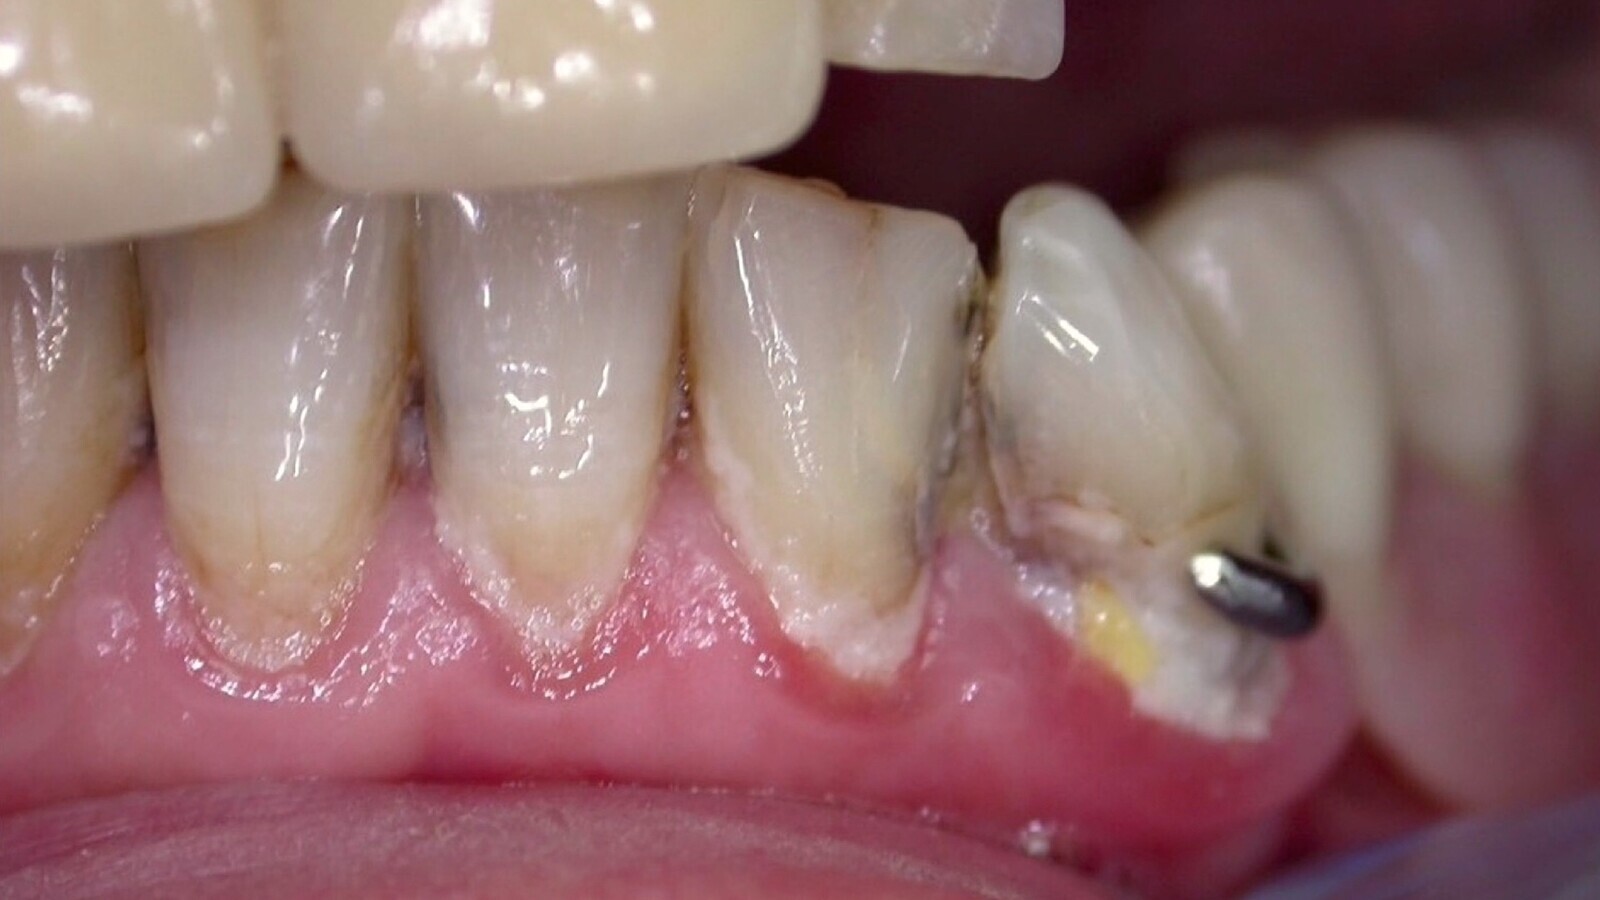

Figura 2. Paciente de bajo riesgo de caries, con una higiene aceptable. En casos de riesgo bajo de caries se recomienda realizar una revisión cada 6 meses.